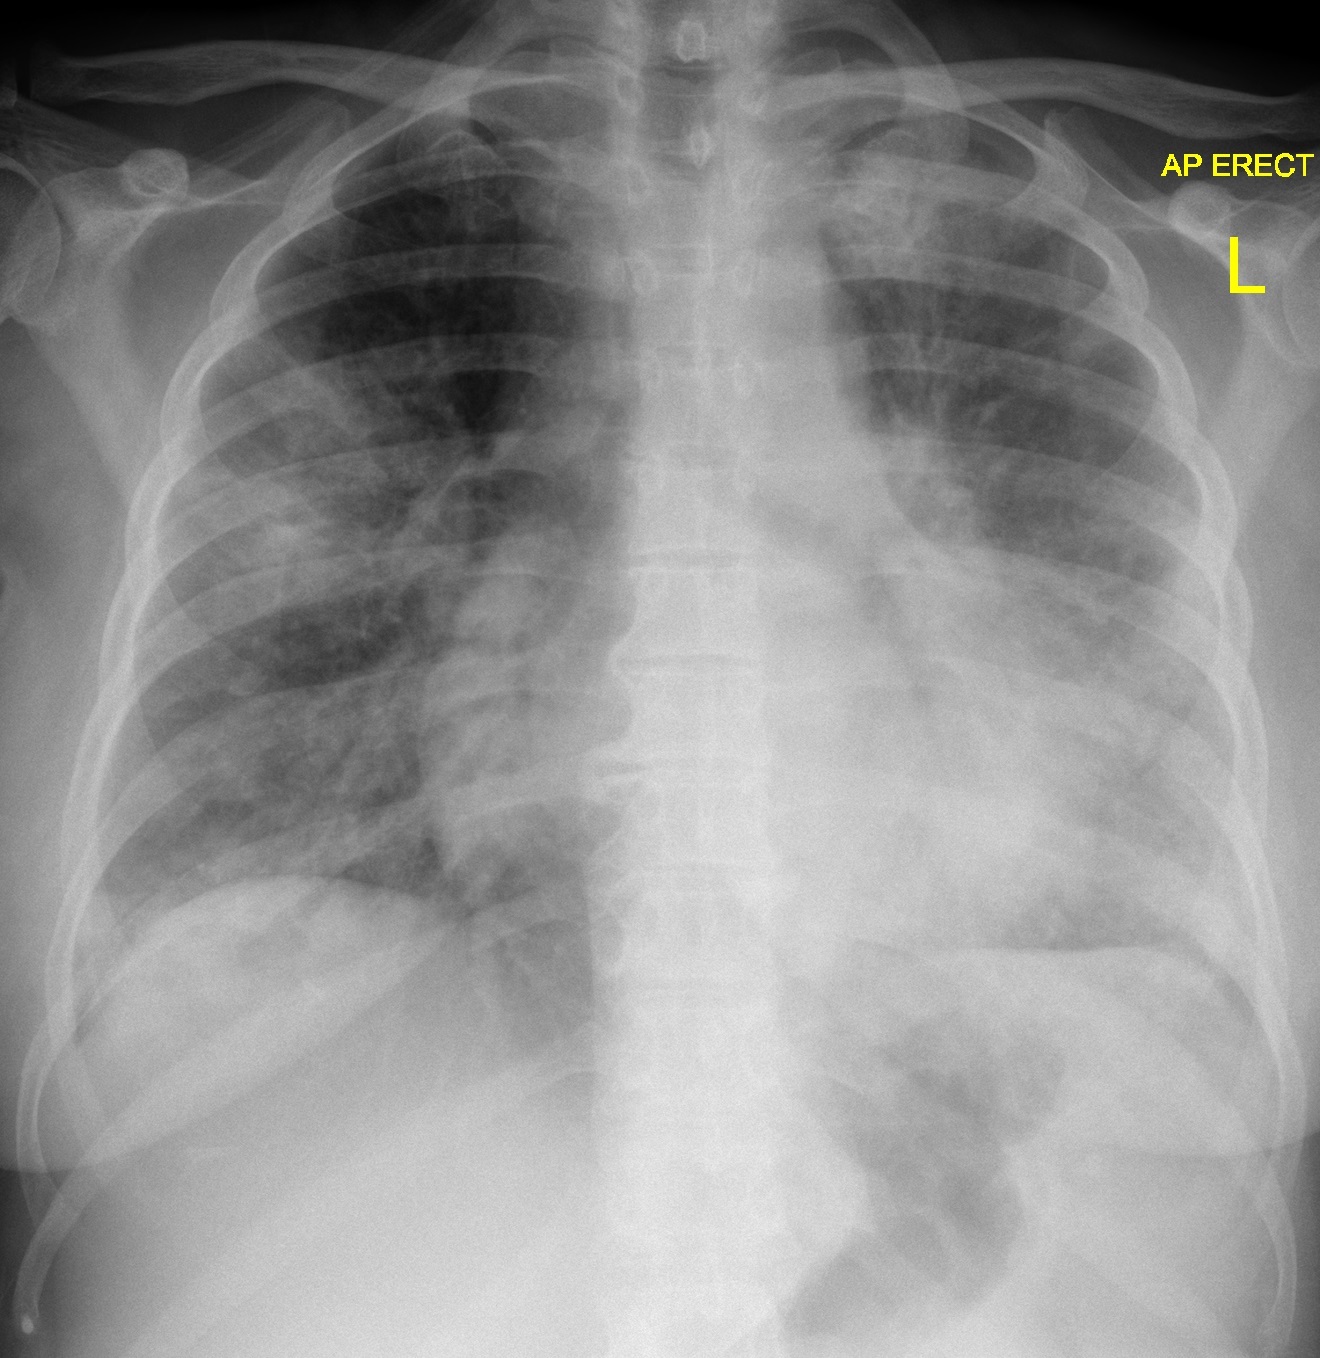

Chest x-ray features of legionella pnuemonia are non-specific but includes a mid-to-lower zone predominance of patchy consolidation. Pleural effusions are seen in around 30%.